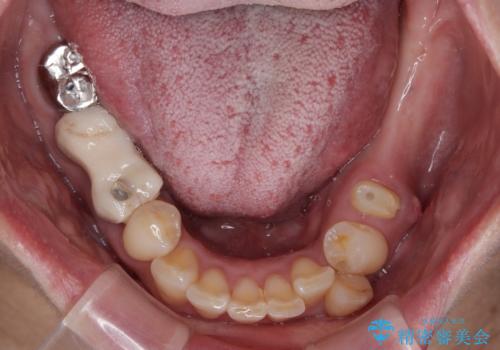

低侵襲なインプラント|痛くないインプラント|エンドペリオ病変|虫歯治療|セラッミクインレー

銀歯を白くしたい|オールセラミッククラウン

担当医 河野豊嘉